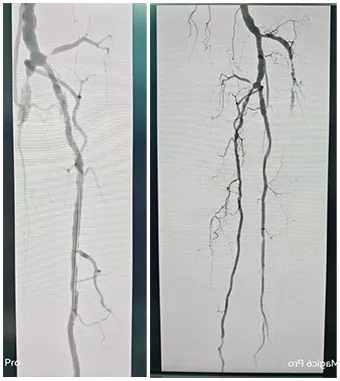

手术˜q‡ç¨‹åQšæœ¯ä¸­é€ åª„½Cø™‚¡‹¹?è…?è†ä¸‹èŠ‚æ®µæ€§ç‹­½H„闭塞,多å‘é’™åŒ–ã€‚ä¿æŠ¤ä¼žä¸‹å‡å®¹ï¼Œä½†è¡€½Ž¡é’™åŒ–局部难以推˜q›ï¼Œå‡å®¹¾l“æŸåŽï¼Œäºˆä»¥¾U¦æŸåž‹è¯ç‰©çƒå›?*150mmã€?*200mm全程处ç†åQŒéž˜å†…造媄昄¡¤ºç‹­çª„ŒDµå®Œå…¨å¤é€šï¼Œå†…膜光整åQŒè¡€‹¹é€šç•…åQŒæœªè§é€ åª„å‰‚å¤–æ¸—ï¼Œæœªè§æ˜Žæ˜¾æ “å¡žã€‚æ‰‹æœ¯é¡ºåˆ©ï¼Œæœ¯åŽæ‚£è€…安˜q”ç—…æˆÑ€?/p>

手术˜q‡ç¨‹åQ?/strong>å¯ég¸å¯¼ç®¡é…åˆå»ºç«‹é€šèµ\åŽï¼Œä½¿ç”¨2.5*150mmã€?*120mmçƒå›Šæ‰©å¼ èƒ«åŽåŠ¨è„‰ç‹­çª„ŒDµï¼Œä½¿ç”¨2*80mmã€?.5*150mmçƒå›Šæ‰©å¼ è…“动脉狭½H„段åQŒé¢„扩åŽä½¿ç”¨¾U¦æŸåž‹è¯ç‰©çƒå›?*120mmã€?*150mm分别扩张胫åŽåŠ¨è„‰ã€è…“åŠ¨è„‰ã€‚å¤æŸ¥é€ åª„½Cºå†…膜光滑,无造媄剂外渗,è†ä¸‹˜qœç«¯åŠ¨è„‰ä¸¤æ”¯æ˜‘Öª„è‰¯å¥½ã€‚æ‰‹æœ¯é¡ºåˆ©ï¼Œæœ¯åŽæ‚£è€…安˜q”ç—…æˆÑ€?/p>

手术˜q‡ç¨‹åQ?/strong>å¯ég¸å¯¼ç®¡é…åˆå»ºç«‹é€šèµ\åŽï¼Œä¿æŠ¤ä¼žä¸‹ä½¿ç”¨4*150mmçƒå›Šé¢„扩张病å˜ï¼Œåˆ†åˆ«äº¤æ¢5*200mm¾U¦æŸåž‹è¯ç‰©çƒå›Šæ‰©å¼ é—­å¡žæ®µåŠè‚¡‹¹…动脉上ŒD늋­½H„处åQ?*150mm¾U¦æŸåž‹è¯ç‰©çƒå›Šæ‰©å¼ èƒ«è…“干开å£ä¸ŠŒDµï¼Œéž˜å†…造媄昄¡¤ºè‚¡æµ…å¼€å£å¤„有残余狭½H„,余闭塞段完全å¤é€šï¼Œå†…膜光整åQŒè¡€‹¹é€šç•…åQŒå¼•å…¥DES6*40m支架一枚予以股‹¹…å¼€å£å¤„释放åQŒå¤æŸ¥é€ åª„æç¤ºç‹­çª„解除åQŒæœªè§é€ åª„剂外渗,è†ä¸‹˜qœç«¯åŠ¨è„‰å„分支显å½Þp‰¯å¥½ï¼Œæœªè§æ˜Žæ˜¾æ “å¡žã€‚æ‰‹æœ¯é¡ºåˆ©ï¼Œæœ¯åŽæ‚£è€…安˜q”ç—…æˆÑ€?/p>